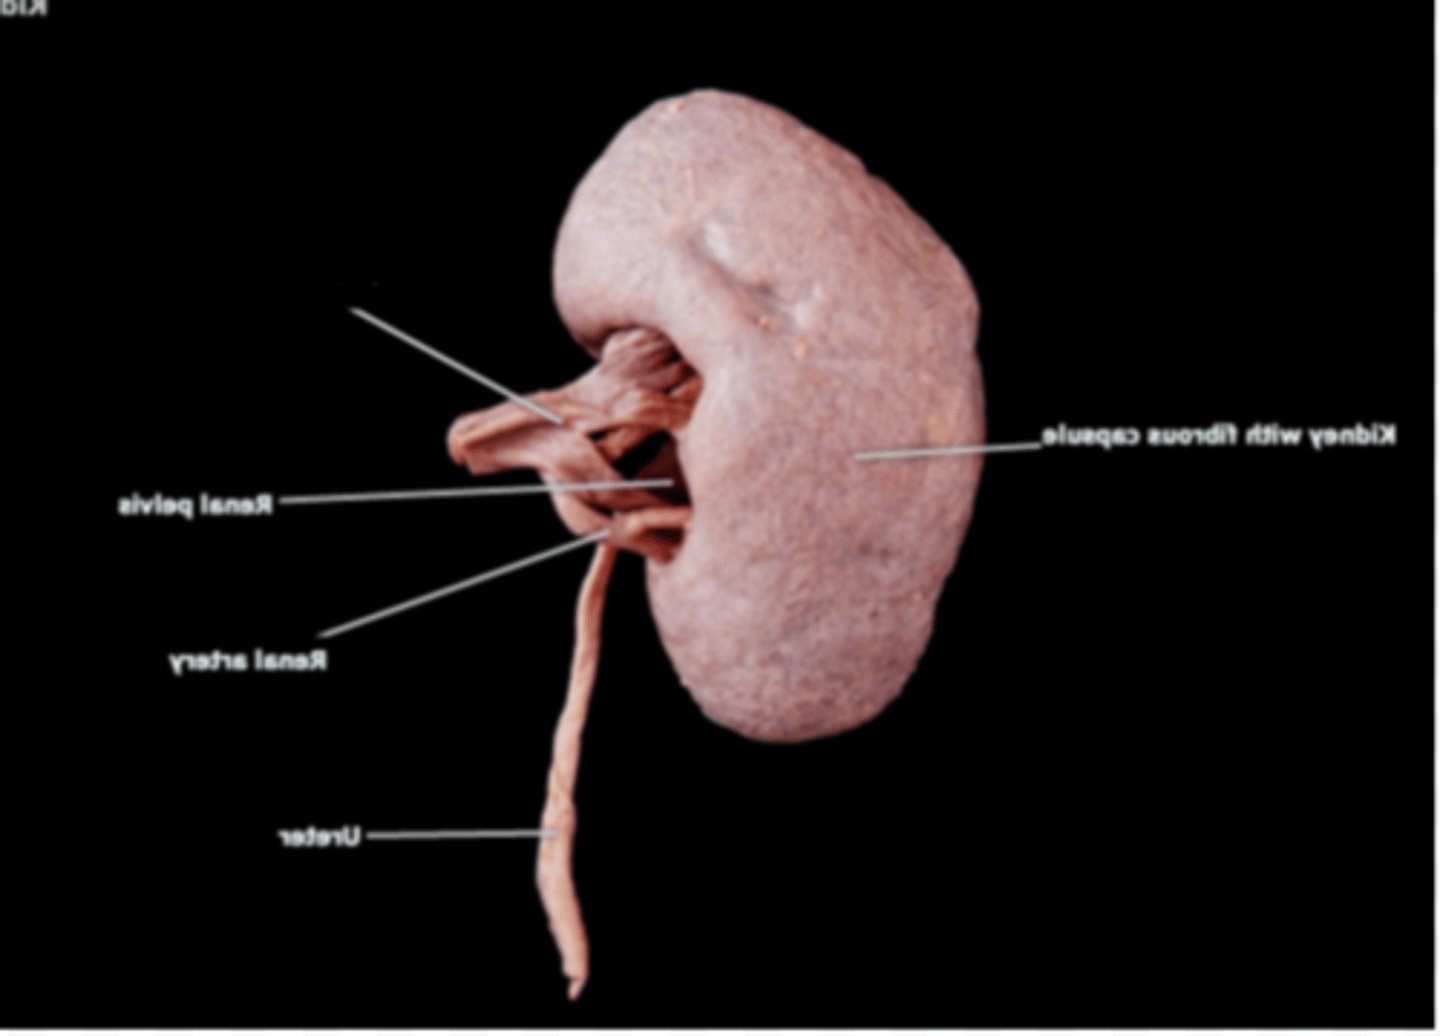

Right Kidney

Left Kidney

Renal Capsule

Renal Pelvis

Renal Hilum

Right Ureter

Left Ureter